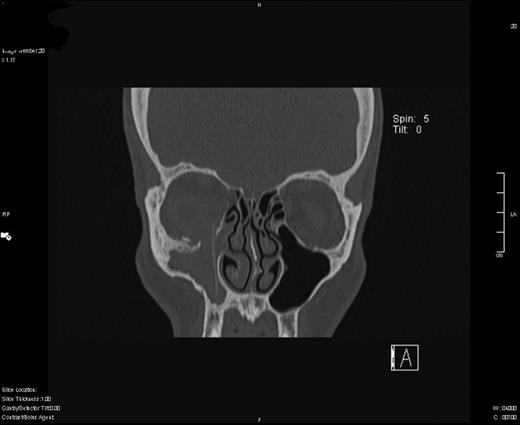

He was treated with systemic and topical antibiotics. On review he reported that his diplopia had worsened, but clinically his eye and swelling was much improved. A CT scan (Fig. 1) showed: ‘A 17 mm defect in his right orbital floor. A (silastic) implant was displaced, lying vertically in the saggital plane. It protrudes through the orbital defect into the medial orbit. The inferior rectus is prolapsed through the orbital floor. Inferior and medial recti are both trapped by the implant’.

Coronal slice of CT scan demonstrating silastic sheet protruding through the right orbital floor.